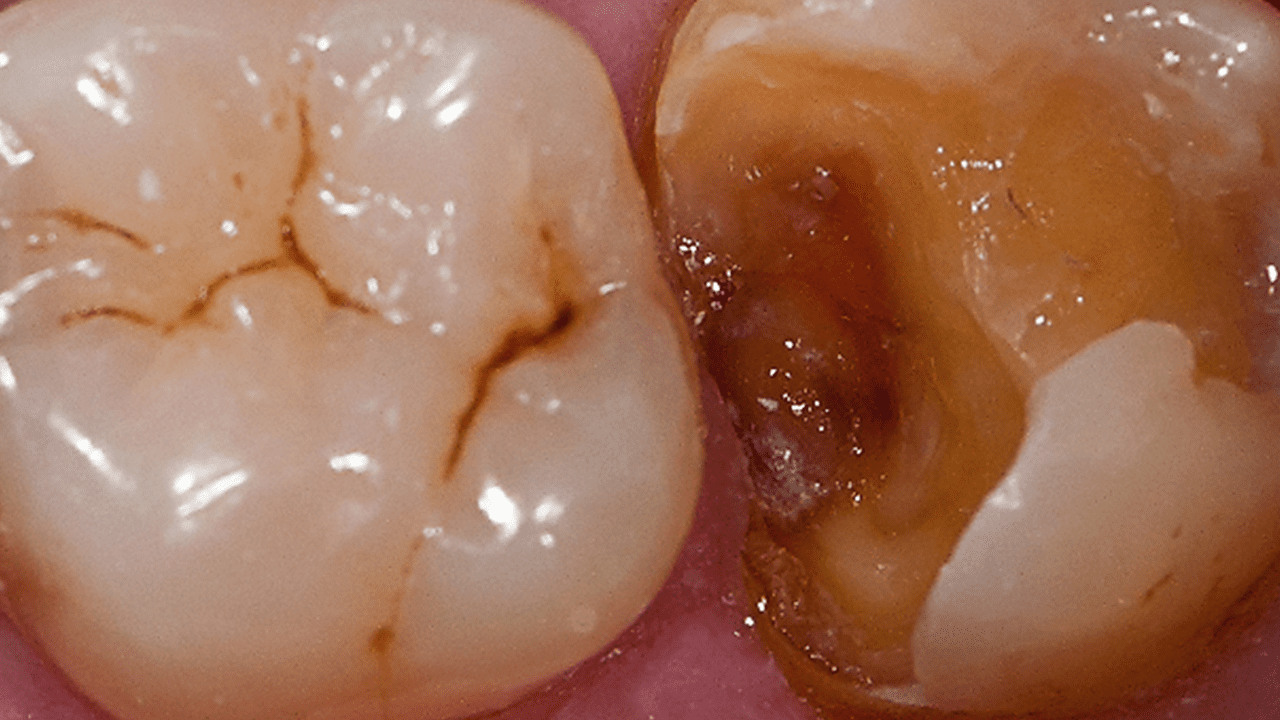

Случай: Мужчина в возрасте 38 лет обратился с неудачной композитной реставрацией дисто-окклюзионной области нижнего моляра, выполненной по II классу. После клинической и рентгенографической диагностики была проведена анестезия, а затем удалена имеющаяся реставрация и проведена очистка кариозной области. Для проведения реставрации дисто-окклюзионной области по II классу было применено комплексное решение.

Вывод: Для снижения риска чувствительности в постоперационном периоде был применен метод селективного протравливания с использованием универсального адгезива. Для идеальной адаптации без зазоров использовался самовыравнивающийся композит объемного внесения SDR plus с низким полимеризационным стрессом. В дополнении, точный контур проксимальной полости и плотный контактный пункт обеспечила секционная матричная система Palodent V3.